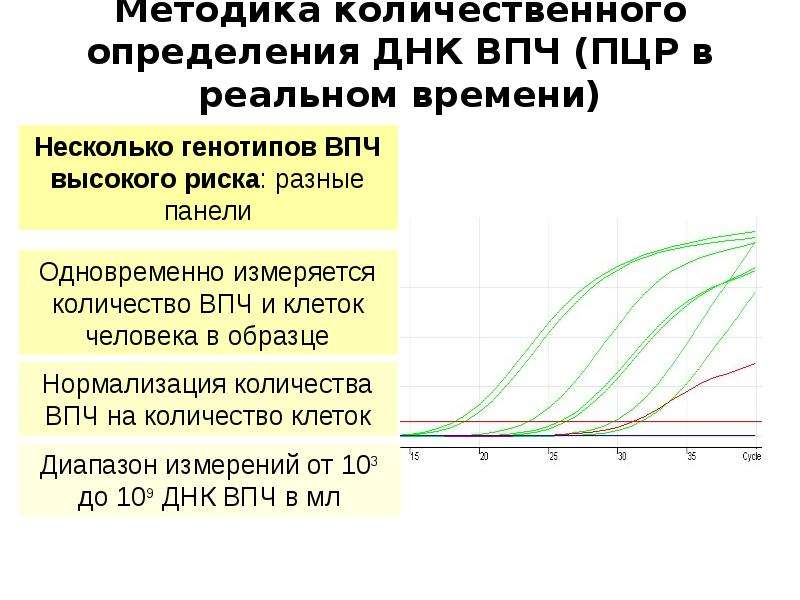

Факторы Риска ВПЧ: Визуальный Обзор и Информация

Раздел: Кладезь мудрости